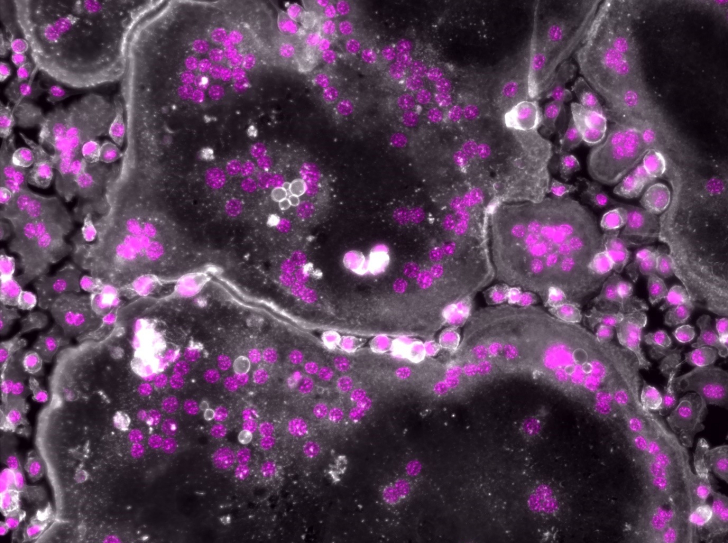

Une piste prometteuse pour augmenter l’efficacité des antibiotiques

Les aminosides sont des antibiotiques efficaces contre de très nombreuses bactéries telles que Escherichia coli, Pseudomonas aeruginosa ou…

Vieillissement, maladies et cancer de l’os : la moésine, une molécule qui pèse dans la balance

Comme un arbre, le squelette est vivant. Il se développe et doit être taillé pour rester harmonieux. Pour maintenir cet état, les ostéoclastes…